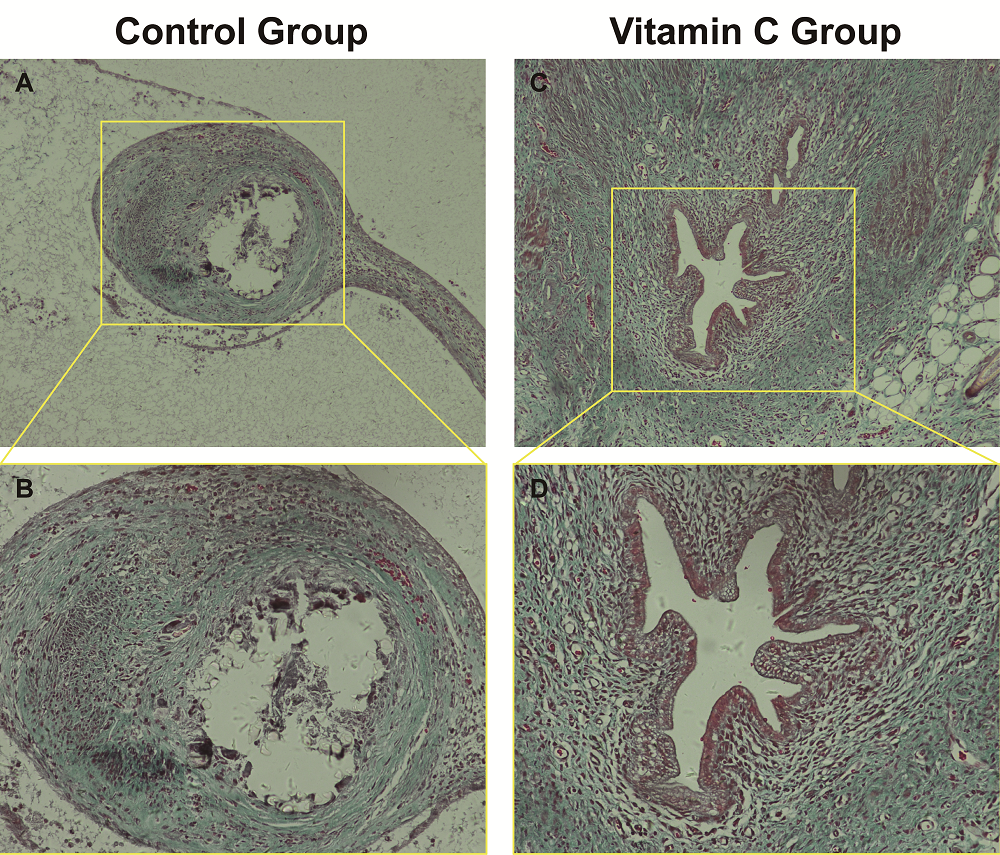

Formation of endometriotic lesions and degree of fibrosis within endometriotic lesions were compared in tissue taken from the two experimental groups. Tissues were fixed in 10% formaldehyde solution for 24 hrs, subsequently embedded in paraffin, and serially sectioned. Tissue sections were stained with hematoxylin and Masson’s stain. After complete resection of the bilateral and subperitoneal endometriotic lesions in the vitamin C and control groups, several samples were randomly selected from each group for Masson’s staining. Under light microscopy, epithelial cells were semiquantitatively evaluated and scored as follows: 3 = 1/4 well-preserved epithelial layer; 2 = 1/4 degree preserved epithelium and leukocyte infiltration; 1 = 1/4 poorly preserved epithelium (occasional epithelial cells); 0 = no epithelial cells observed [7]. Matrix elements surrounding the tissue and the degree of fibrosis were assessed by Masson’s staining as follows: Grade 0, no fibrosis; Grade 1, minimum fibrous tissue growth; Grade 2, irregular fibrous tissue growth; Grade 3, concentric fibers and transparency [8, 9]. In the vitamin C group, four endometriotic lesions from different rats were randomly selected for analysis. In the control group, five endometriotic lesions were randomly selected from different rats. Three pathologists examined the nine lesions (Table 3) in a blinded fashion. The remaining lesions of both groups were used for quantitative, real-time PCR (RT-PCR).

In tissue sections, the degree of fibrosis as highlighted by Masson’s staining of endometriotic lesions was significantly less in the vitamin C group than in the control group (P < 0.05) (Figure 5). Three pathologists blindly examined all tissue sections, and the fibrosis score of the vitamin C group was significantly less than that in the control group (Table 3). Additionally, collagen type I, α-SMA, CTGF, and TGF-β1 expression in immunohistochemical staining was significantly lower in the vitamin C group than in the control group (Figure 6). Moreover, the degree of fibrosis around endometriotic lesions in rats was significantly reduced in the vitamin C group compared with the control group.

Figure 5.

Figure 5.— Comparison of the degree of fibrosis between the two experimental groups by Masson’s staining. (A and B) and (C and D) represent Masson’s staining of endometriotic lesions in control group and vitamin C group respectively. (A, C: 100 ×; B, D: 200 ×).